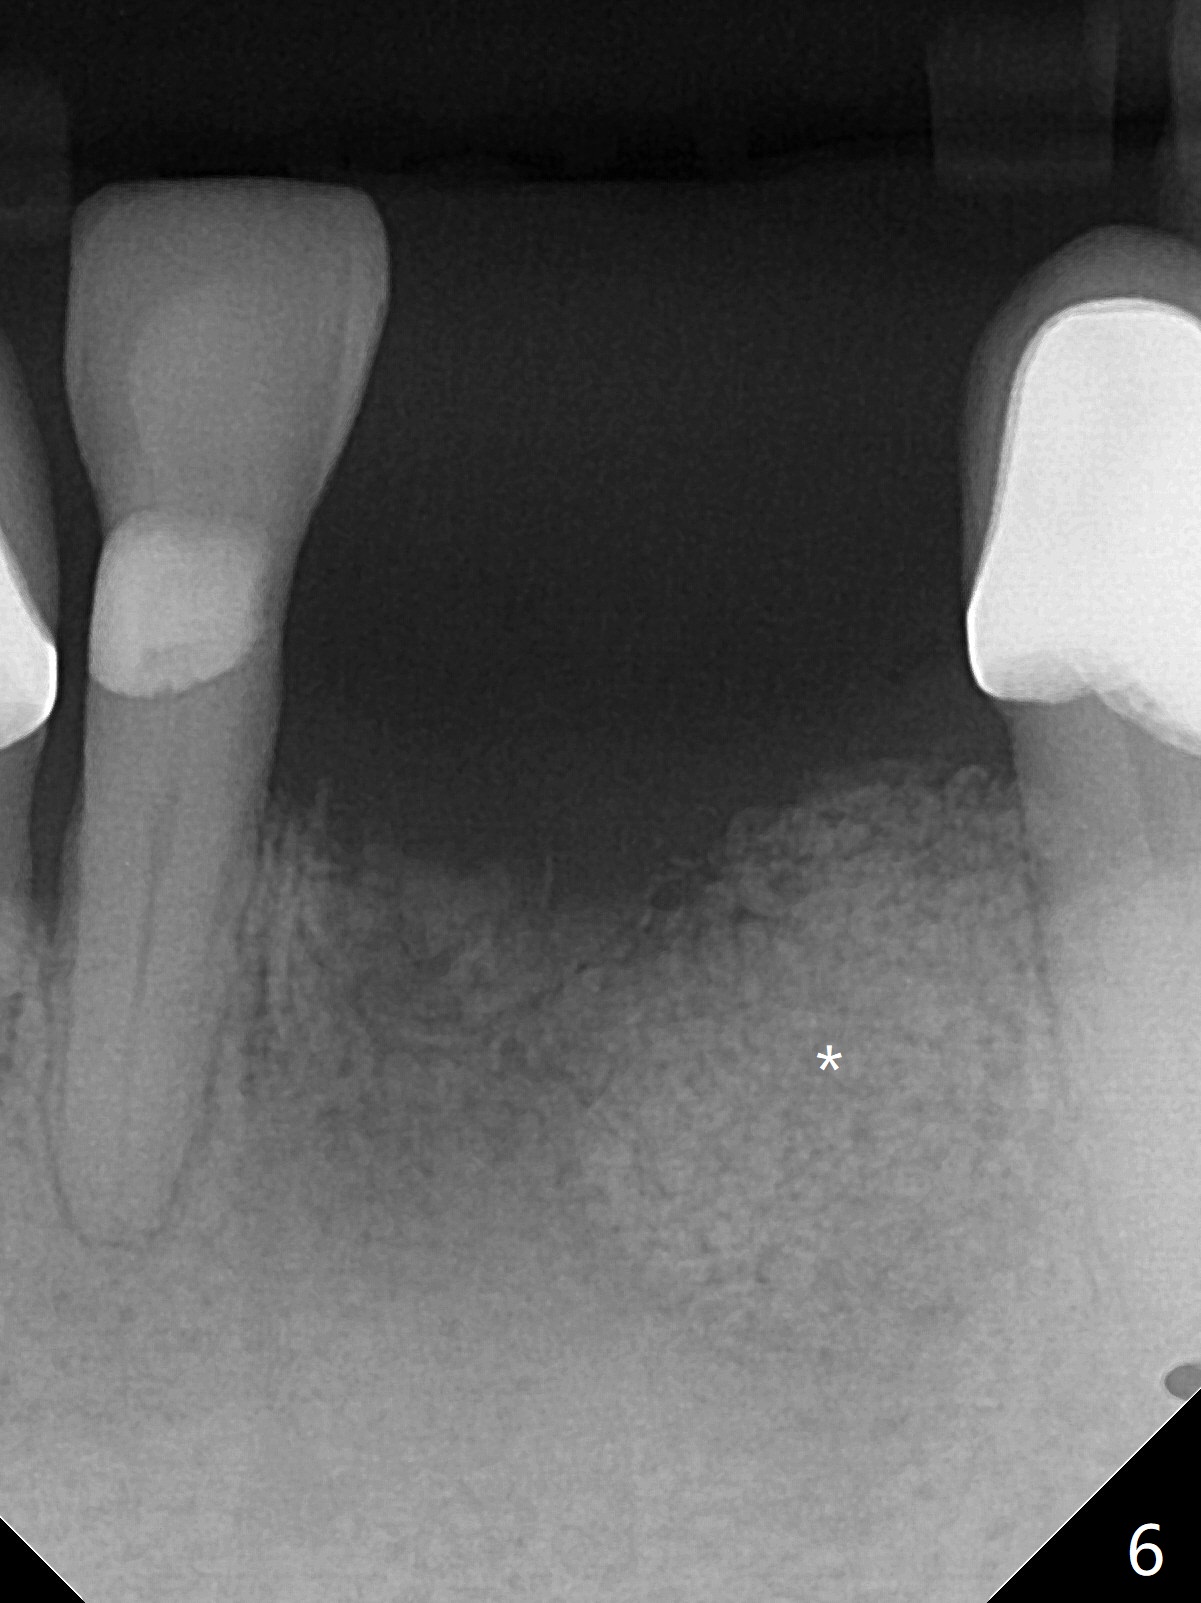

A 64-year-old woman requests extraction of the tooth #23 for lower partial (Fig.1). Since there are 2 buccal sinus tracks, another residual root is suspected (?). After shown loss of the buccal plate (Fig.2,3), the patient agrees to have socket preservation with allograft (Fig.5,6 *) and BioXclude (Fig.4 >). The suspected residual root is not explored considering the 2 sinus tracks being associated with the lesion of #23 (Fig.2,3). Cytoplast is not used because of time constraint and fear of gingival dehiscence associated with extensive dissection. In fact the sinus tracks shrink in a week, while the buccal plate remains bulging (Fig.7 *) and the socket heals (Fig.8 >). The buccal plate is flat (no swelling) 1 month postop (Fig.9).